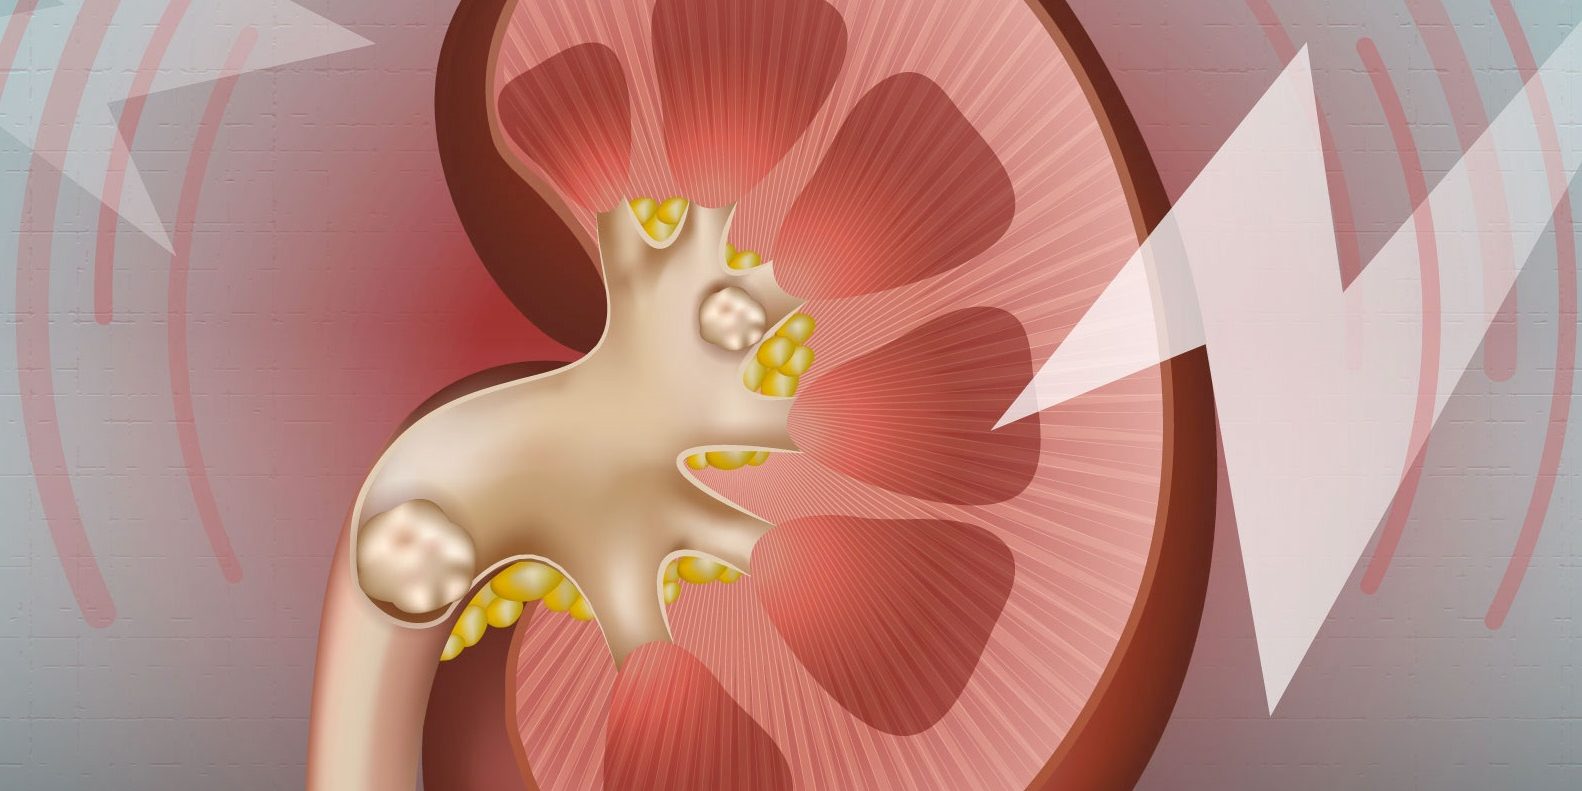

Οι πέτρες νεφρών μπορεί να ποικίλουν σε μέγεθος και υφή και αποτελούνται από στρώματα ασβεστίου, παρόμοια με άλλες ιζηματογενείς αποθέσεις στη φύση.

Οι πέτρες αποτελούνται κατά κύριο λόγο από μια ουσία που ονομάζεται οξαλικό ασβέστιο , η οποία πιστεύεται – μέχρι τώρα – ότι είναι αδιάλυτη στους νεφρούς.

Η ανάλυση αποκάλυψε ότι οι πέτρες στα νεφρά είναι φτιαγμένες από “εναλλασσόμενα νανοστρώματα πλούσια σε οργανικές ύλες και ορυκτά” από κρυστάλλους. Επιπλέον, αυτά τα στρώματα είναι «εντυπωσιακά όμοια» με άλλες αρχαίες ιζηματογενείς αποθέσεις, όπως «θαλάσσιων στρωματολιτών, ωιδίων και κελυφών και μαργαριταριών», μεταξύ άλλων.

Είναι σημαντικό ότι η μελέτη αποκάλυψε επίσης ότι ορισμένα από αυτά τα στρώματα είχαν υποβαθμιστεί, δημιουργώντας κρυστάλλους. Οι εικόνες έδειξαν ότι οι νέοι κρύσταλλοι είχαν αρχίσει να αναπτύσσονται, υποδηλώνοντας ότι οι πέτρες στα νεφρά “υποβάλλονται σε πολλαπλά στάδια διάλυσης, καθώς κρυσταλλώνονται και αναπτύσσονται μέσα στον νεφρό”.